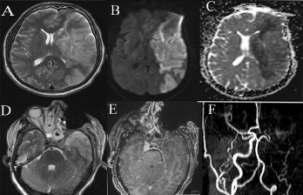

Emphysematouspyelonephritis–inanon-diabeticyoungwomen

—arareassociation— Y S Ravikumar, K M Srinath, L S Adarsh, Manjunath S Shetty, Subrahmanyam Karuturi, B Balaji Kirushnan .................................................108 Rhinocerebralmucormycosis:reportoftwocasesandreviewofliterature — Gopee E Makwana, Vikash Jain, Nandini Bahri, Mala Sinha, Manish Kumar Mathur.................110 Harlequinichthyosis—acasereport— Sendhil Coumary A, Seethesh Ghose .................................113 ..............................................................................................................................................116